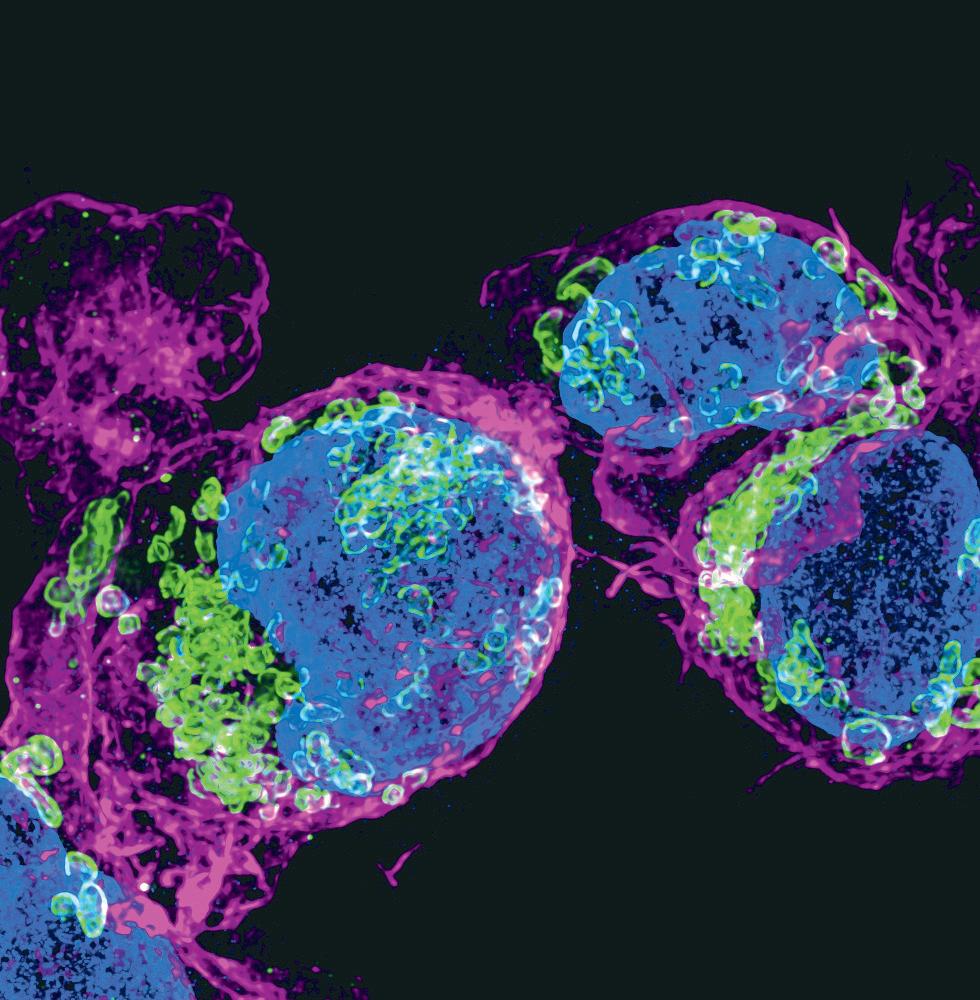

Fotografie na obálce: „Cellular harmony: The Interplay of action, mitochondria and the nucleus in B cells“. Vítězný mikrosnímek soutěže CELLIM Best Microscopy, Picture Contest 2024, autorem je Narenda Varma Gottumukkala, Masarykova univerzita, CEITEC, výzkumná skupina Michala Šmídy.